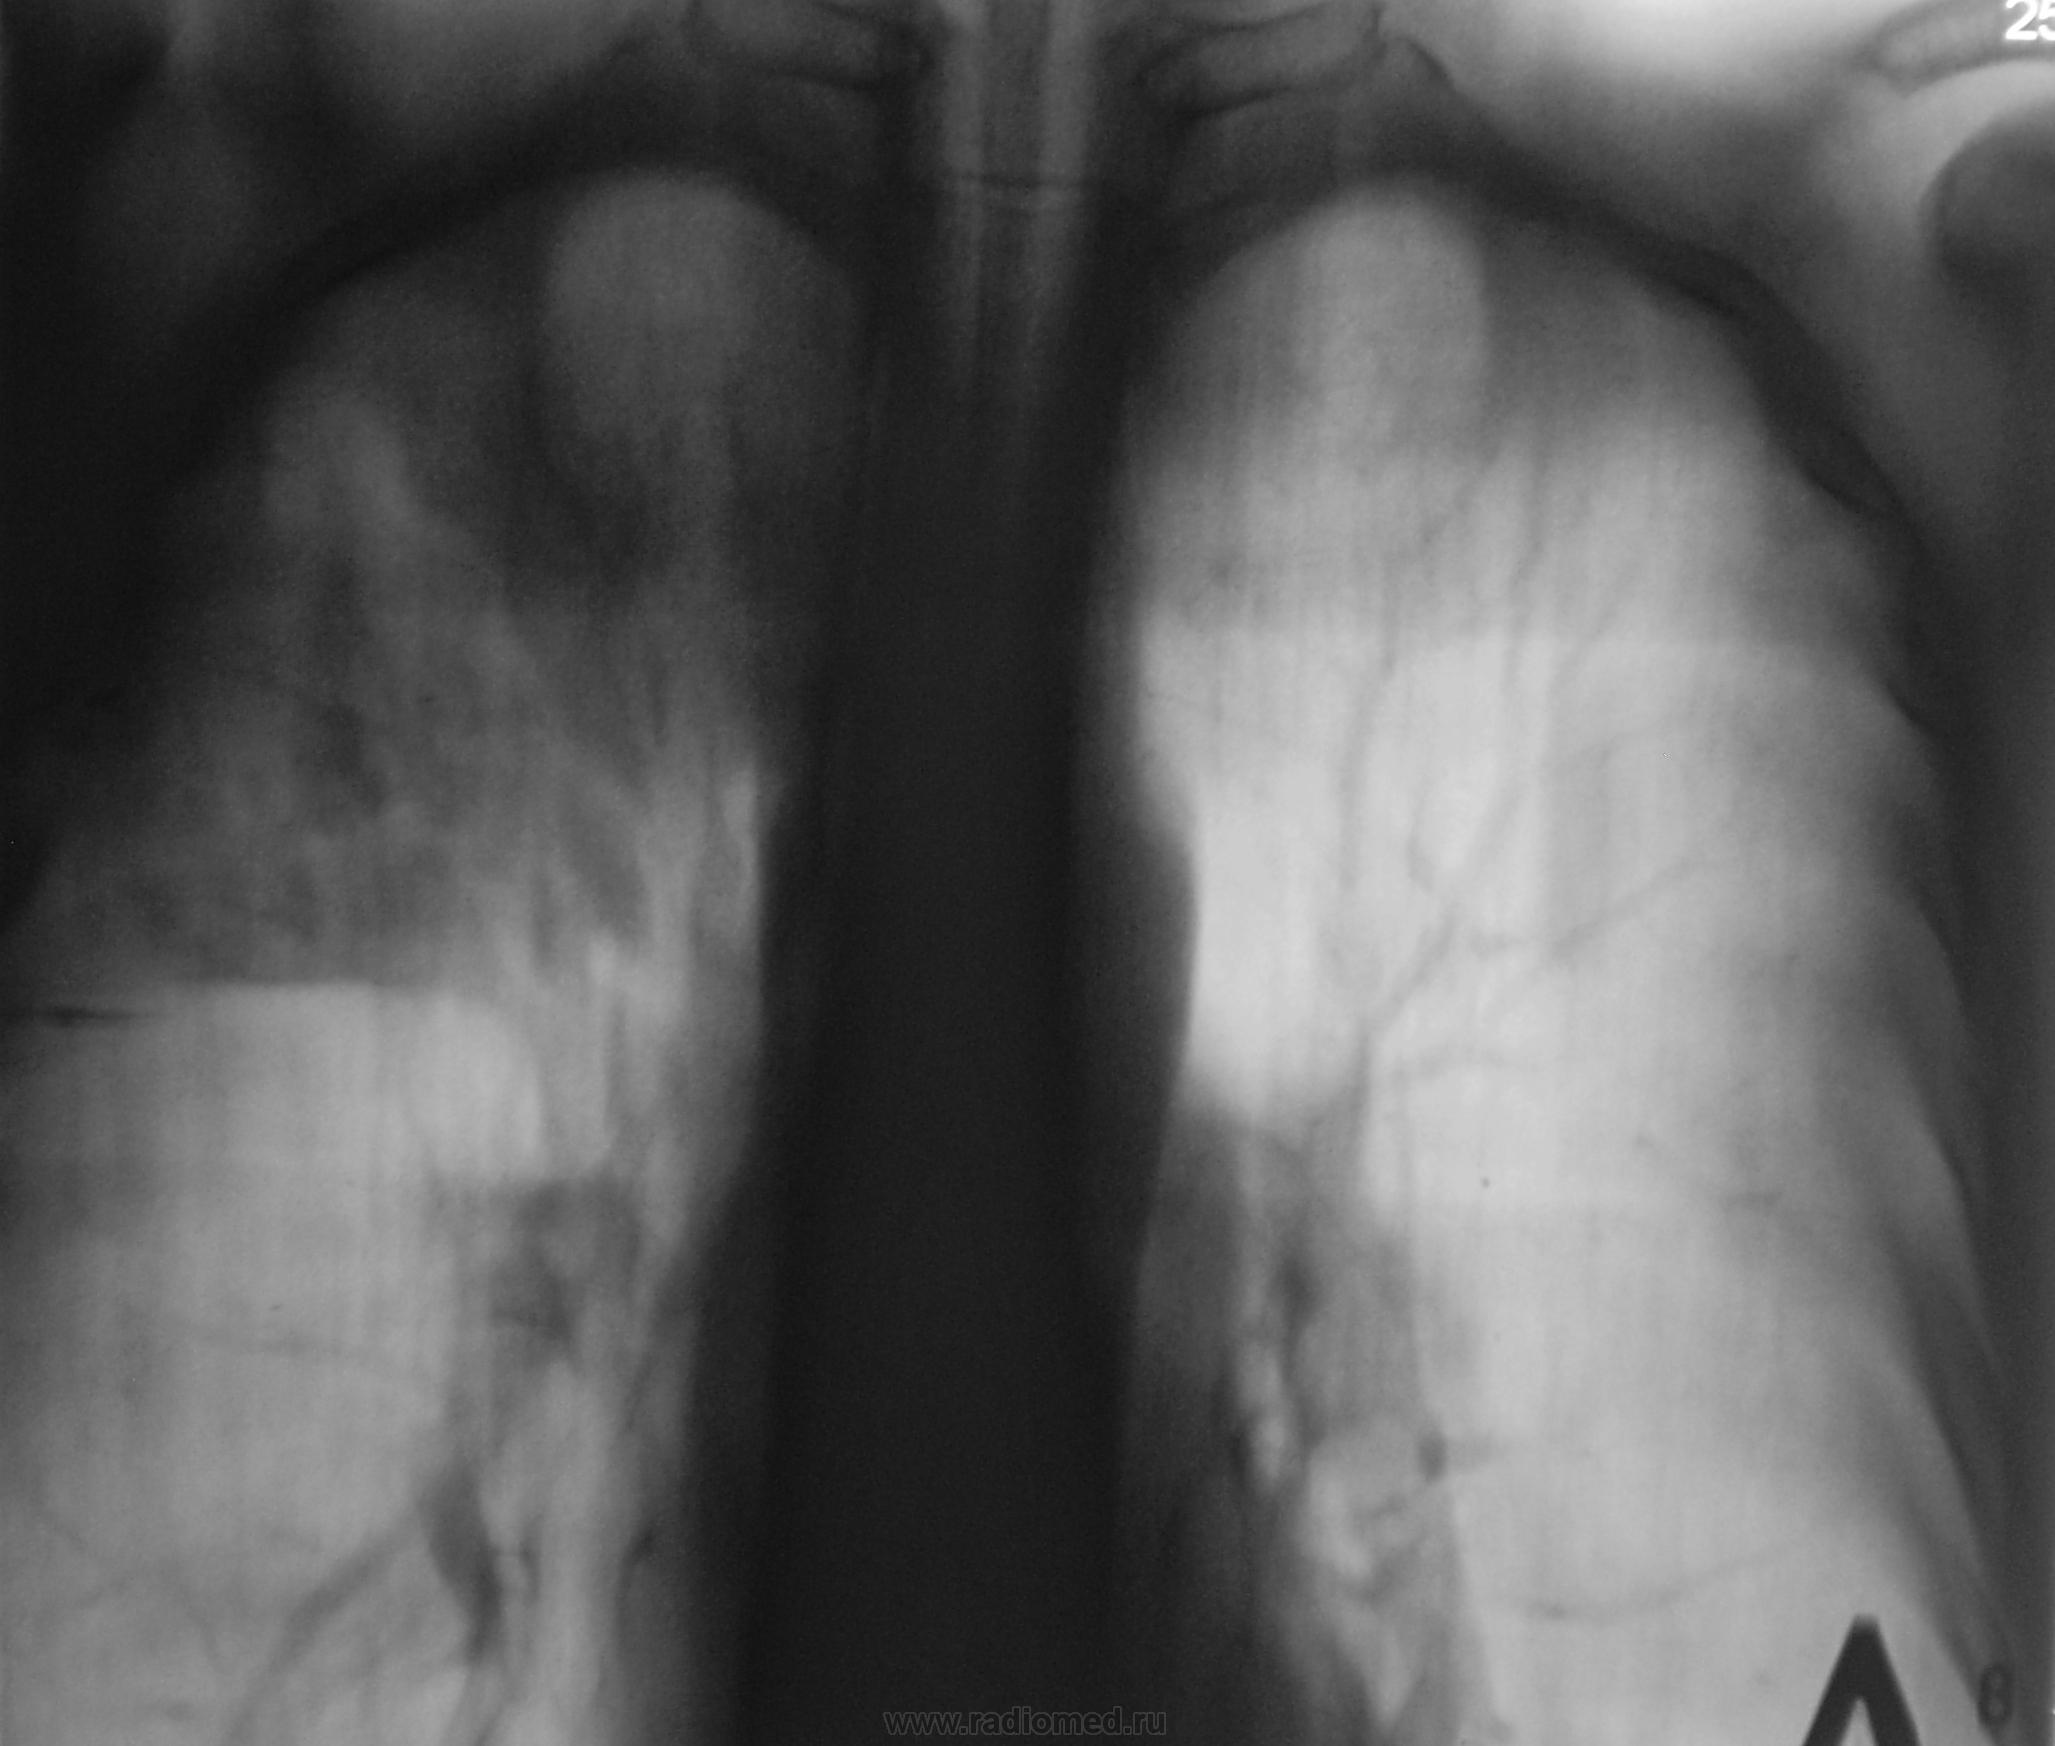

А, через 6 месяцев стало так.

А, через 6 месяцев стало так...

Мы, после этого дообследования (последнего) упаковали пациента в ОПТД, там взяли, обнаружили палки и пациент начал лечиться

А, вчера был контроль после проведенного лечения, по поводу специфического процесса.

Мои сомнения в природе фокуса - локализация  тени в 3 сегменте, где туберкулёму  никогда я не встречал.Но это не означает, что такой локализации нет. Кальцинаты в тени ориентировали  меня на специфический процесс, но расположение фокуса  не давало  полной уверенности в этом. Если у кого будет в практике туберкулема в S3, прошу показать на сайте. Томографические слои в период развития туберкулезного процесса не соответствуют исходным. Доказать взаимосвязь этих  изменений не представляется возможным. Поэтому я хотел посмотреть  боковую рентгенограмму, чтобы узнать состояние  круглой тени.  Возможно, что эти два процесса самостоятельны. Вопрос важный, так как некоторые врачи утверждают, что из туберкулёмы не развивается инфильтративный туберкулёз лёгких.  Интересно знать, какой диагноз выставили больному врачи фтизиатры? С уважением Nikoilas.

В ОПТД (вторые снимки) был выставлен инфильтративный.